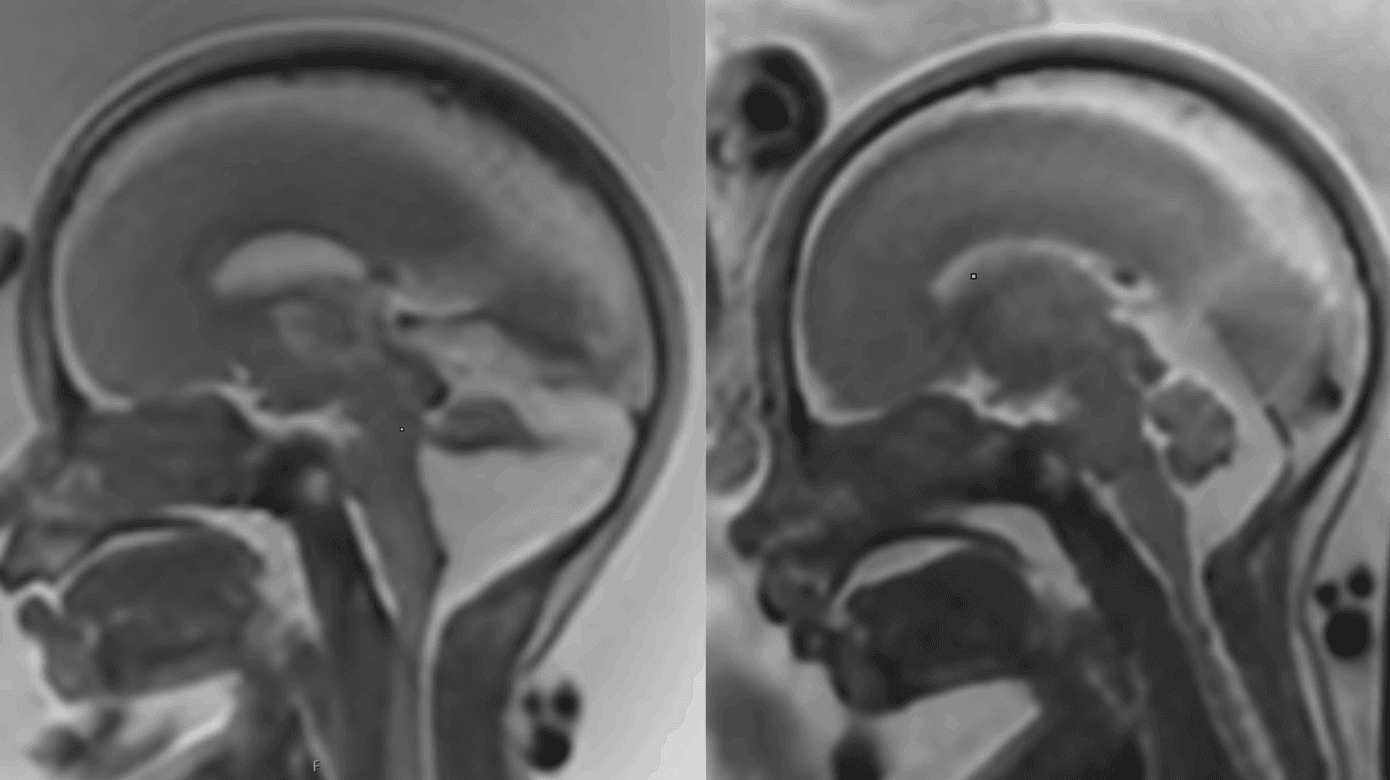

Føtal MR-skanning er en vigtig supplerende undersøgelse til føtalmedicinsk specialist neurosonografi. Formålet er at be- eller afkræfte UL-fund og undersøge for andre/associerede CNS-misdannelser, som kan være væsentlige for en samlet vurdering af prognosen (Figur 4) [15].

MR-skanning har nogle fordele og komplimenterer derfor føtal UL-skanning. MR-skanning er uafhængig af fosterlejring, højt BMI hos den gravide og oligohydramnios. Der kan ved MR-skanning visualiseres flere detaljer ved mistanke om fossa posterior anomalier, ligesom blødninger, vaskulære forandringer, migrationsdefekter og andre malformationer af den kortikale udvikling fremstilles bedre ved MR-skanning. Derimod har UL-skanning en højere spatial opløsning end MR-skanning og kan bedre visualisere f.eks. cystevægge og flow i kar med Doppler. MR-skanning kræver længere undersøgelsestid, hvilket kan være problematisk ved ubehag hos den gravide eller mange fosterbevægelser.

I Danmark foretages ca. 150 MR-fosterskanninger om året ligeligt fordelt mellem København og Aarhus. De fleste MR-skanninger foretages som opfølgning på UL-skanning i 2. trimester. Hyppige indikationer er f.eks. abnorm hjernebiometri, ventrikulomegali, tegn på fokal patologi som iskæmi eller blødning, fossa posterior malformation, midtlinjeanomalier som corpus callosum agenesi og i visse tilfælde ved infektionssygdomme, som kan medføre fosterhjerneskade. Ved mistanke om defekter i spinalkanalen kan nærmere detaljer ved et evt myelomeningocele påvises.

I 3. trimester anvendes MR-skanning ved opfølgning af tilstande, hvor der er behov for planlægning af forløsning og intervention postnatalt.